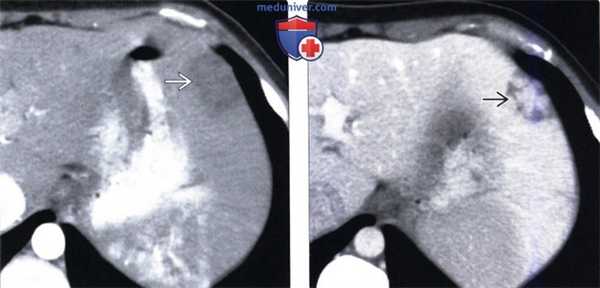

(Слева) На КТ в артериальной фазе контрастного усиления у мужчины 31 года с нарушением функции печени, носовыми кровотечениями и кровохарканьем определяется большие артерио-венозные мальформации (АВМ) в базальных отделах правого легкого. Контрастное усиление печени имеет «пятнистый» характер, расширенные печеночные вены преждевременно заполняются контрастом.

(Справа) На КТ у этого же пациента визуализируются дискретные АВМ в печени, а также не столь четко различимые телеангиэктазии меньшего размера. Паренхима печени выглядит «пестрой». (Слева) На КТ у этого же пациента в печени видны дискретные АВМ, паренхима печени выглядит «пестрой», печеночная артерия значительно расширена.

(Справа) На КТ срезе у этого же пациента определяется выраженное расширение печеночной артерии; паренхима пече ни имеет «пестрый» вид. (Слева) На КТ срезе (этот же пациент) визуализируется артерио-портальный шунт и расширенная печеночная артерия.

(Справа) На корональной КТ (объемный рендеринг) у этого же пациента визуализируются ABM в легких. Врожденная геморрагическая телеангиэктазия (синдром Ослера-Вебера-Рандю) — наследственное заболевание, приводящее к фиброваскулярной дисплазии, в результате чего появляется возможность для развития телеангиэктазий и АВМ во множестве органов, преимущественно в коже, легких, печени и ЖКТ.